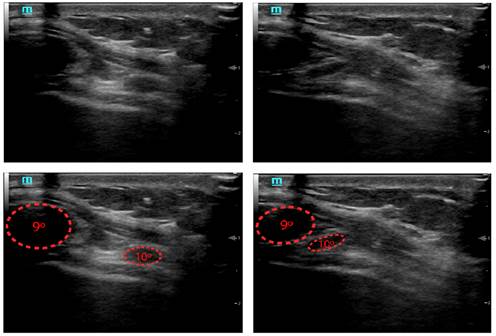

La exploración física (EF) revela hiperalgesia anteromedial a la palpación en últimos arcos costales derechos. El dolor se reproduce con la maniobra del gancho (hook maneuver). En el resto de la exploración no se objetivan alteraciones. Se hace una ecografía clínica, donde se observa hipermovilidad de las costillas octava, novena, décima y undécima. De nuevo con la maniobra del gancho, se muestra deslizamiento de la décima costilla sobre la novena, lo que evoca la clínica.

Se han publicado estudios que evalúan la capacidad de la ecografía clínica para confirmar la presencia de SCD1,2 (figura 2). Se muestra de especial utilidad la maniobra del empuje, con una sensibilidad cuantificada en el 87%2. Para ejecutarla, la médica o el médico coloca el pulgar y los dedos índice y medio bajo la costilla de interés y hace una presión creciente en sentido posterior y superior para tratar de demostrar laxitud o desplazamiento. También resulta favorable la utilización de la maniobra de crunch. En ella, se pide al paciente que haga una contracción de los músculos abdominales mientras eleva lentamente la cabeza y el tronco.